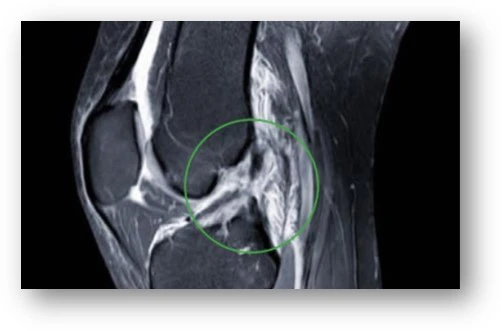

Häufig wird am Ort der Verletzung (z.B Skigebiet) zunächst eine knöcherne Verletzung ausgeschlossen. Sofern aber der Verdacht auf eine Bandverletzung vorliegt, wird häufig eine Empfehlung zur Weiterbehandlung am Wohnort ausgeprochen. Endgültig Aufschluss über Art und Schwere der Verletzung gibt dann die MRI-Untersuchung.